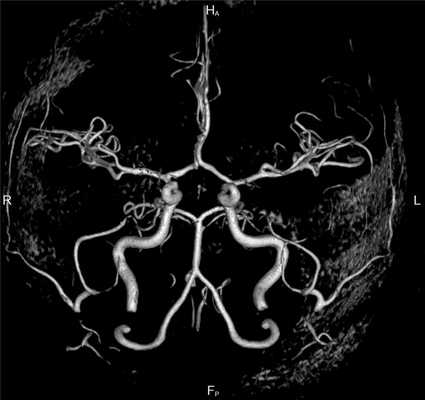

МРА-картина выраженной асимметрии венозной сети с преобладанием и нерезкой дилатацией вен правой гемисферы (поперечного, сигмовидного синусов и яремной вены справа); гипоплазии левого поперечного и сигмовидного синуса. Единичные участки (2) локального расширения вен в парасагиттальных отделах левой гемисферы, большой вены мозга. Асимметричная, расширенная и выражено извитая венозная структура экстракраниальных отделов справа.